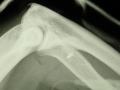

La rupture basse du biceps est beaucoup moins fréquence que celle de sa longue portion proximale et son traitement en est totalement différent. Elle touche volontiers l'homme de la quatrième décade avec un sur-risque chez le fumeur. Le traitement non chirurgical ne donne pas un bon résultat sur la force de flexion et de supination de l'avant-bras avec une relative fatigabilité de ces gestes. Néanmoins, la chirurgie ouverte "classique" nécessite une longue incision sinueuse antérieure et inesthétique et le taux de complications -notamment nerveuses- est relativement élevé.